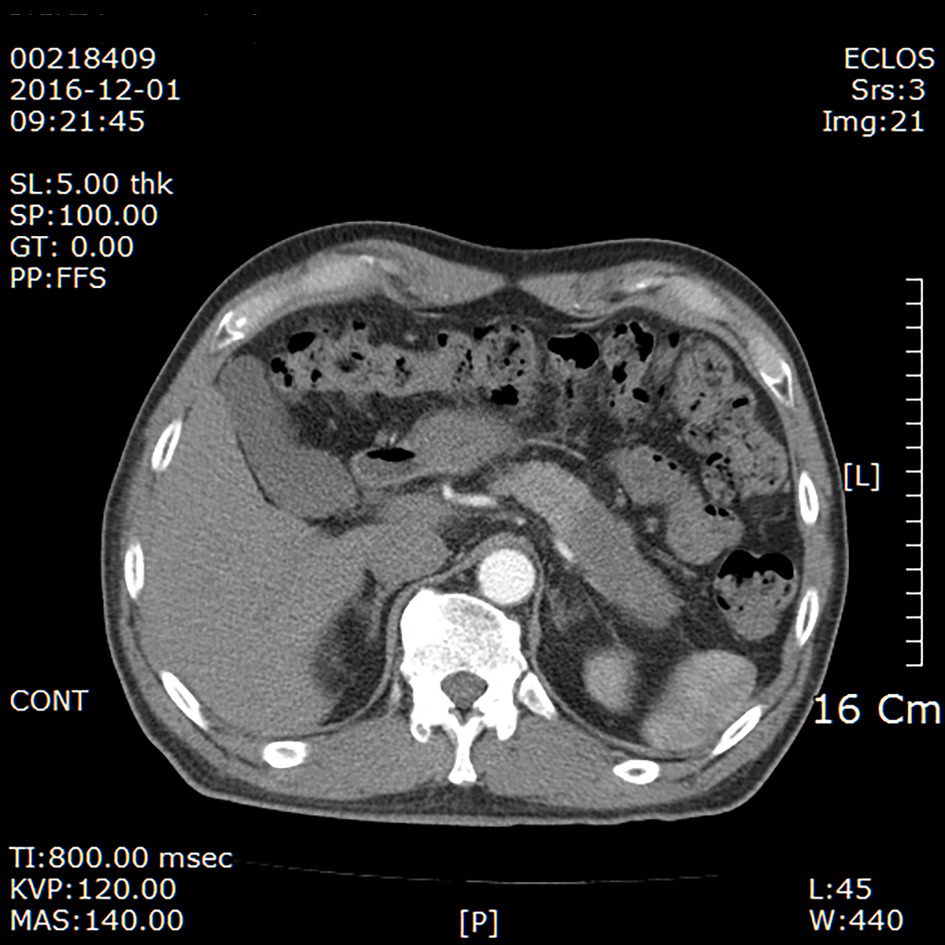

췌장의 종괴 및 전이 여부 등 많은 정보들을 ct로 확인할 수 있다. 췌장암이란 췌장에 생긴 암세포로 이루어진 종괴를 말한다. Za očkování volno nebo mimořádný bonus. 복부 전산화단층촬영(ct) 또는 자기공명영상술(mri)에 의해 영상 진단을 얻음으로써 진단 과정이 시작됩니다. 4월부터 항암치료를 시작해서 벌써 5개월이라는 시간이 지났네요 그동안 많은 일이 있었지만 언제나 웃으면서 씩씩하게 지내는 엄마를 보면서 저도 항상 힘을 냅니다. 최근에는 ct 등을 찍는 일이 많아서 우연히 발견되는 초중기 췌장암도 늘고 있다. 췌장암 진단할 때 가장 중요한 검사가 복부 ct이다. States, as well as several canadian provinces and central american countries.

강남세브란스병원에서 췌장 절제술을 받은 145명을 분석한 결과, 췌장암 환자의 당뇨병 유병률은 75.0%로 비췌장암 환자의 38.5%보다 크게. 복부 전산화단층촬영(ct) 또는 자기공명영상술(mri)에 의해 영상 진단을 얻음으로써 진단 과정이 시작됩니다. 췌장암이란 췌장에 생긴 암세포로 이루어진 종괴를 말한다. Interested in helping us improve the quality and quantity? 컴퓨터단층촬영(ct)에서 지름 2㎝의 췌장암이 발견돼 간담췌외과, 소화기내과, 영상의학과, 종양내과, 방사선종양학과 등으로 구성된 다학제 진료를 받았다.

셰이나 테일러,'아슬아슬 비키니 입고 눈맞춤' 췌장암. 컴퓨터단층촬영(ct)에서 지름 2㎝의 췌장암이 발견돼 간담췌외과, 소화기내과, 영상의학과, 종양내과, 방사선종양학과 등으로 구성된 다학제 진료를 받았다.